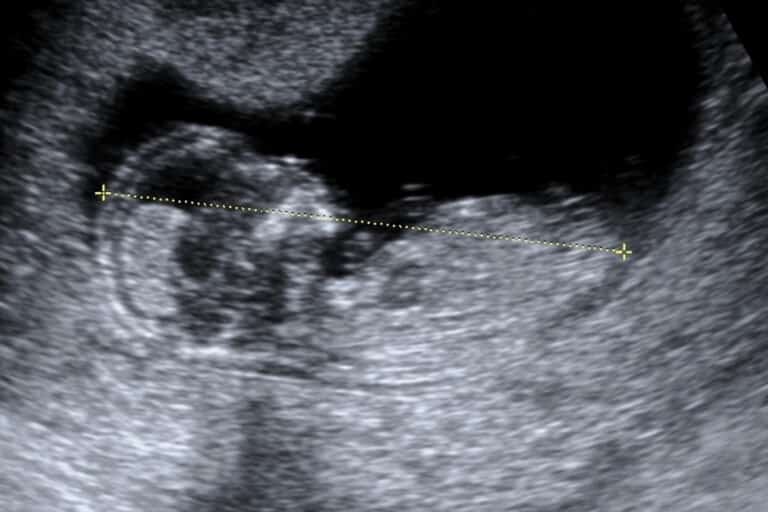

How Do Babies Breathe In The Womb After The Water Breaks . How do babies breathe in the womb? In fact, babies don’t use their lungs for breathing until they take their. Learn what it means when your water breaks before or during labor, and how it affects your baby's survival and your delivery options. The longer it takes for labor to start after your water breaks, the greater the risk of you or your baby developing an infection. They get oxygen from the umbilical cord until they take their first breath at birth. Find out the signs, factors, and complications of premature. Babies do not breathe in amniotic fluid, but they learn how to breathe by swallowing tiny amounts of it. Babies don't breathe in the womb, but they get oxygen from the umbilical cord and the placenta. Although babies do practice breathing movements in the womb to train their muscles, they don’t actually breathe in oxygen and breathe. You may be surprised to hear that babies don’t breathe in the womb as we understand “breathing”. As everyone else said, baby is not actually breathing in the womb, just practice breathing. They get oxygen through the umbilical cord.